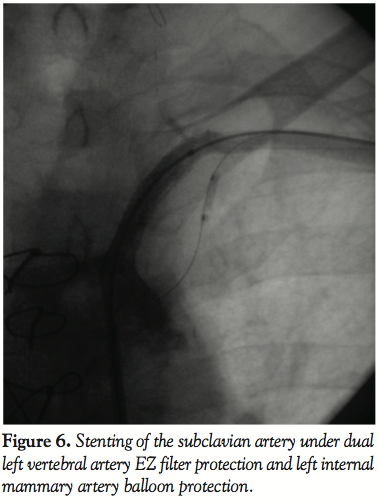

Protection to both the VA and LIMA from the expected embolic shower during SC artery angioplasty was achieved by positioning a FilterWire EZ (Boston Scientific Corporation, Natick, Massachusetts) in the proximal part of the left vertebral artery and a 2.5 mm Maverick balloon (Boston Scientific Corporation) in the mouth of the LIMA via the left brachial artery route, after performing systemic heparinization and achieving an  activated coagulation time of  around 300 seconds.

A 0.014˝ Choice PT graphix guidewire (Boston Scientific Corporation) was passed through the SC lesion via the transbrachial route with some difficulty. The guidewire was then advanced down into the iliac artery and pulled out of the femoral introducer using a GooseNeck snare (ev3, Inc., North Plymouth, Minnesota) (Figures 3 and 4). The wire was then introduced within a 5 Fr, 11 cm pediatric sheath (Cordis Corporation, Miami, Florida). A 5 Fr multipurpose guiding catheter (GC) was later advanced over the 0.014˝ wire and positioned just near the ostium of the left SC artery. The lesion was then predilated with a 2 x 20 mm and then a 3 x 20 mm Maverick balloon (Figure 5). Only then could the GC advance across the distal portion of the vessel to the lesion. At this moment, the 0.014˝ wire was removed and exchanged for a 0.035˝ wire (260 cm in length) through the GC. Then, the 5 Fr introducer femoral sheath was  exchanged for a 7 Fr, 61 cm SL2 sheath (St. Jude Medical, Daig Division, Minnetonka, Minnesota) positioned just near the ostium of the left subclavian and subsequently a 7 x 37 mm Express LD stent (Boston Scientific Corporation) was deployed in situ (Figure 6). Advancement of the GC across the lesion after predilation as well as all inflations within the SC artery were protected with prior LIMA 2.5 mm balloon inflation at 6 atm with subsequent deflation 5 seconds after deflating the subclavian balloon or stent. Post-dilatation of the stent was not performed. The LIMA balloon was withdrawn, then the Filterwire was retrieved with its  retrieval sheath (Boston Scientific Corporation) through the brachial sheath without any difficulty (Figure 7). The patient tolerated the procedure well and there were no complications. Some debris was retrieved in the Filterwire.